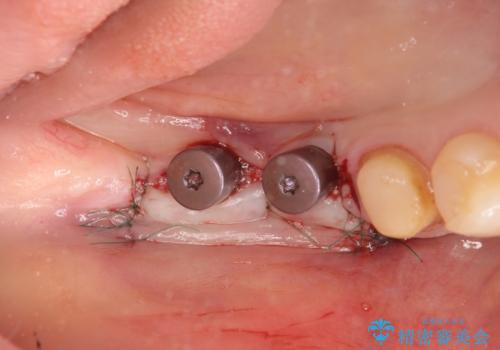

インプラント治療による咬合機能回復

- 失ってしまった奥歯の咬合機能の回復を求めて来院されました。

骨の幅が十分にないのでインプラント治療に伴い、人工骨の造成を同時に計画します。

長年安心してしっかりと噛んでいただけるよう今回は骨を増成する治療計画としました。